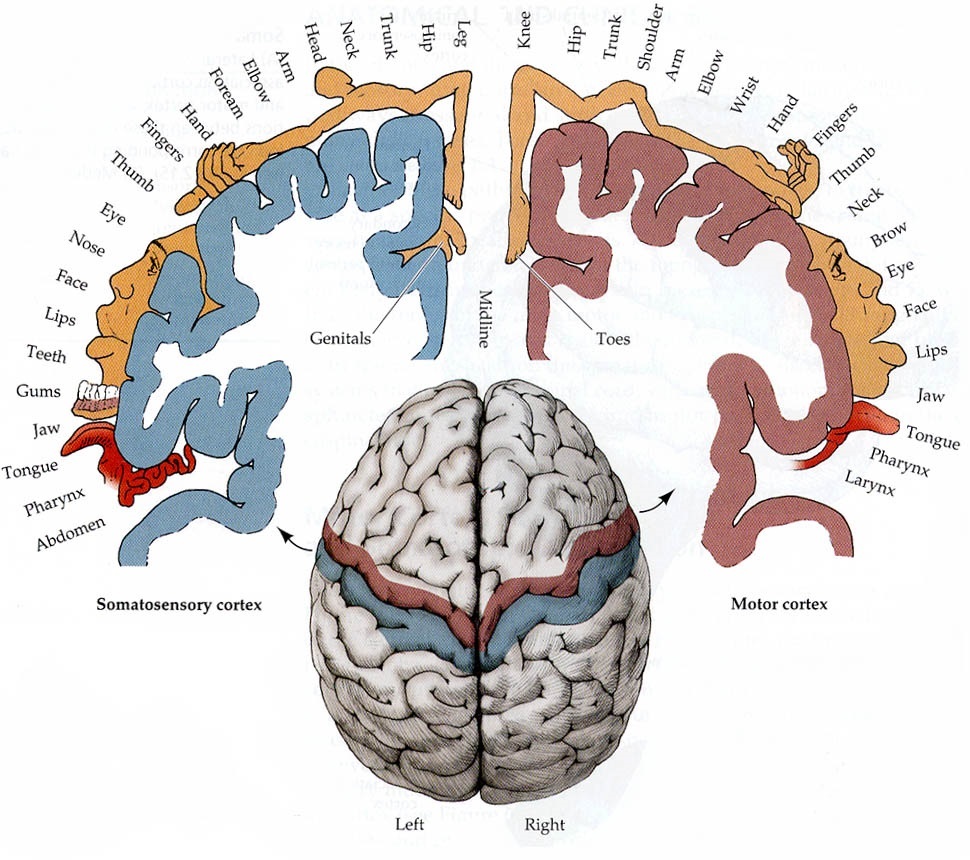

Схема чувствительных зон новой коры мозга